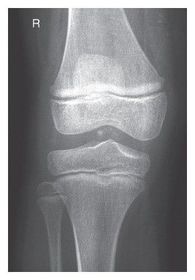

A. medial and lateral intercondylar tubercles B. lateral epicondyle femur C. lateral condyle femur D. lateral condyle tibia E. articular facets tibia (tibial plateau) F. medial condyle tibia G. medial condyle femur H. medial epicondyle femur I. patella

AP Knee pt supine w/ leg rotated internally 5 degrees to get knee in TRUE AP - CR parallel to tibial plateau @ 1/2 in distal to apex of patella *angle CR 3-5 degrees CAUDAL for ASTHENIC pts* *angle CR 3-5 degrees CEPHALIC for HYPERSTHENIC pts* leave CR angled 0 degrees for average sized pts.